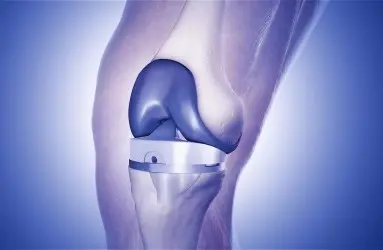

- Diz Protezi

- Total Eklem Protezi (Kalça, diz, diğer)